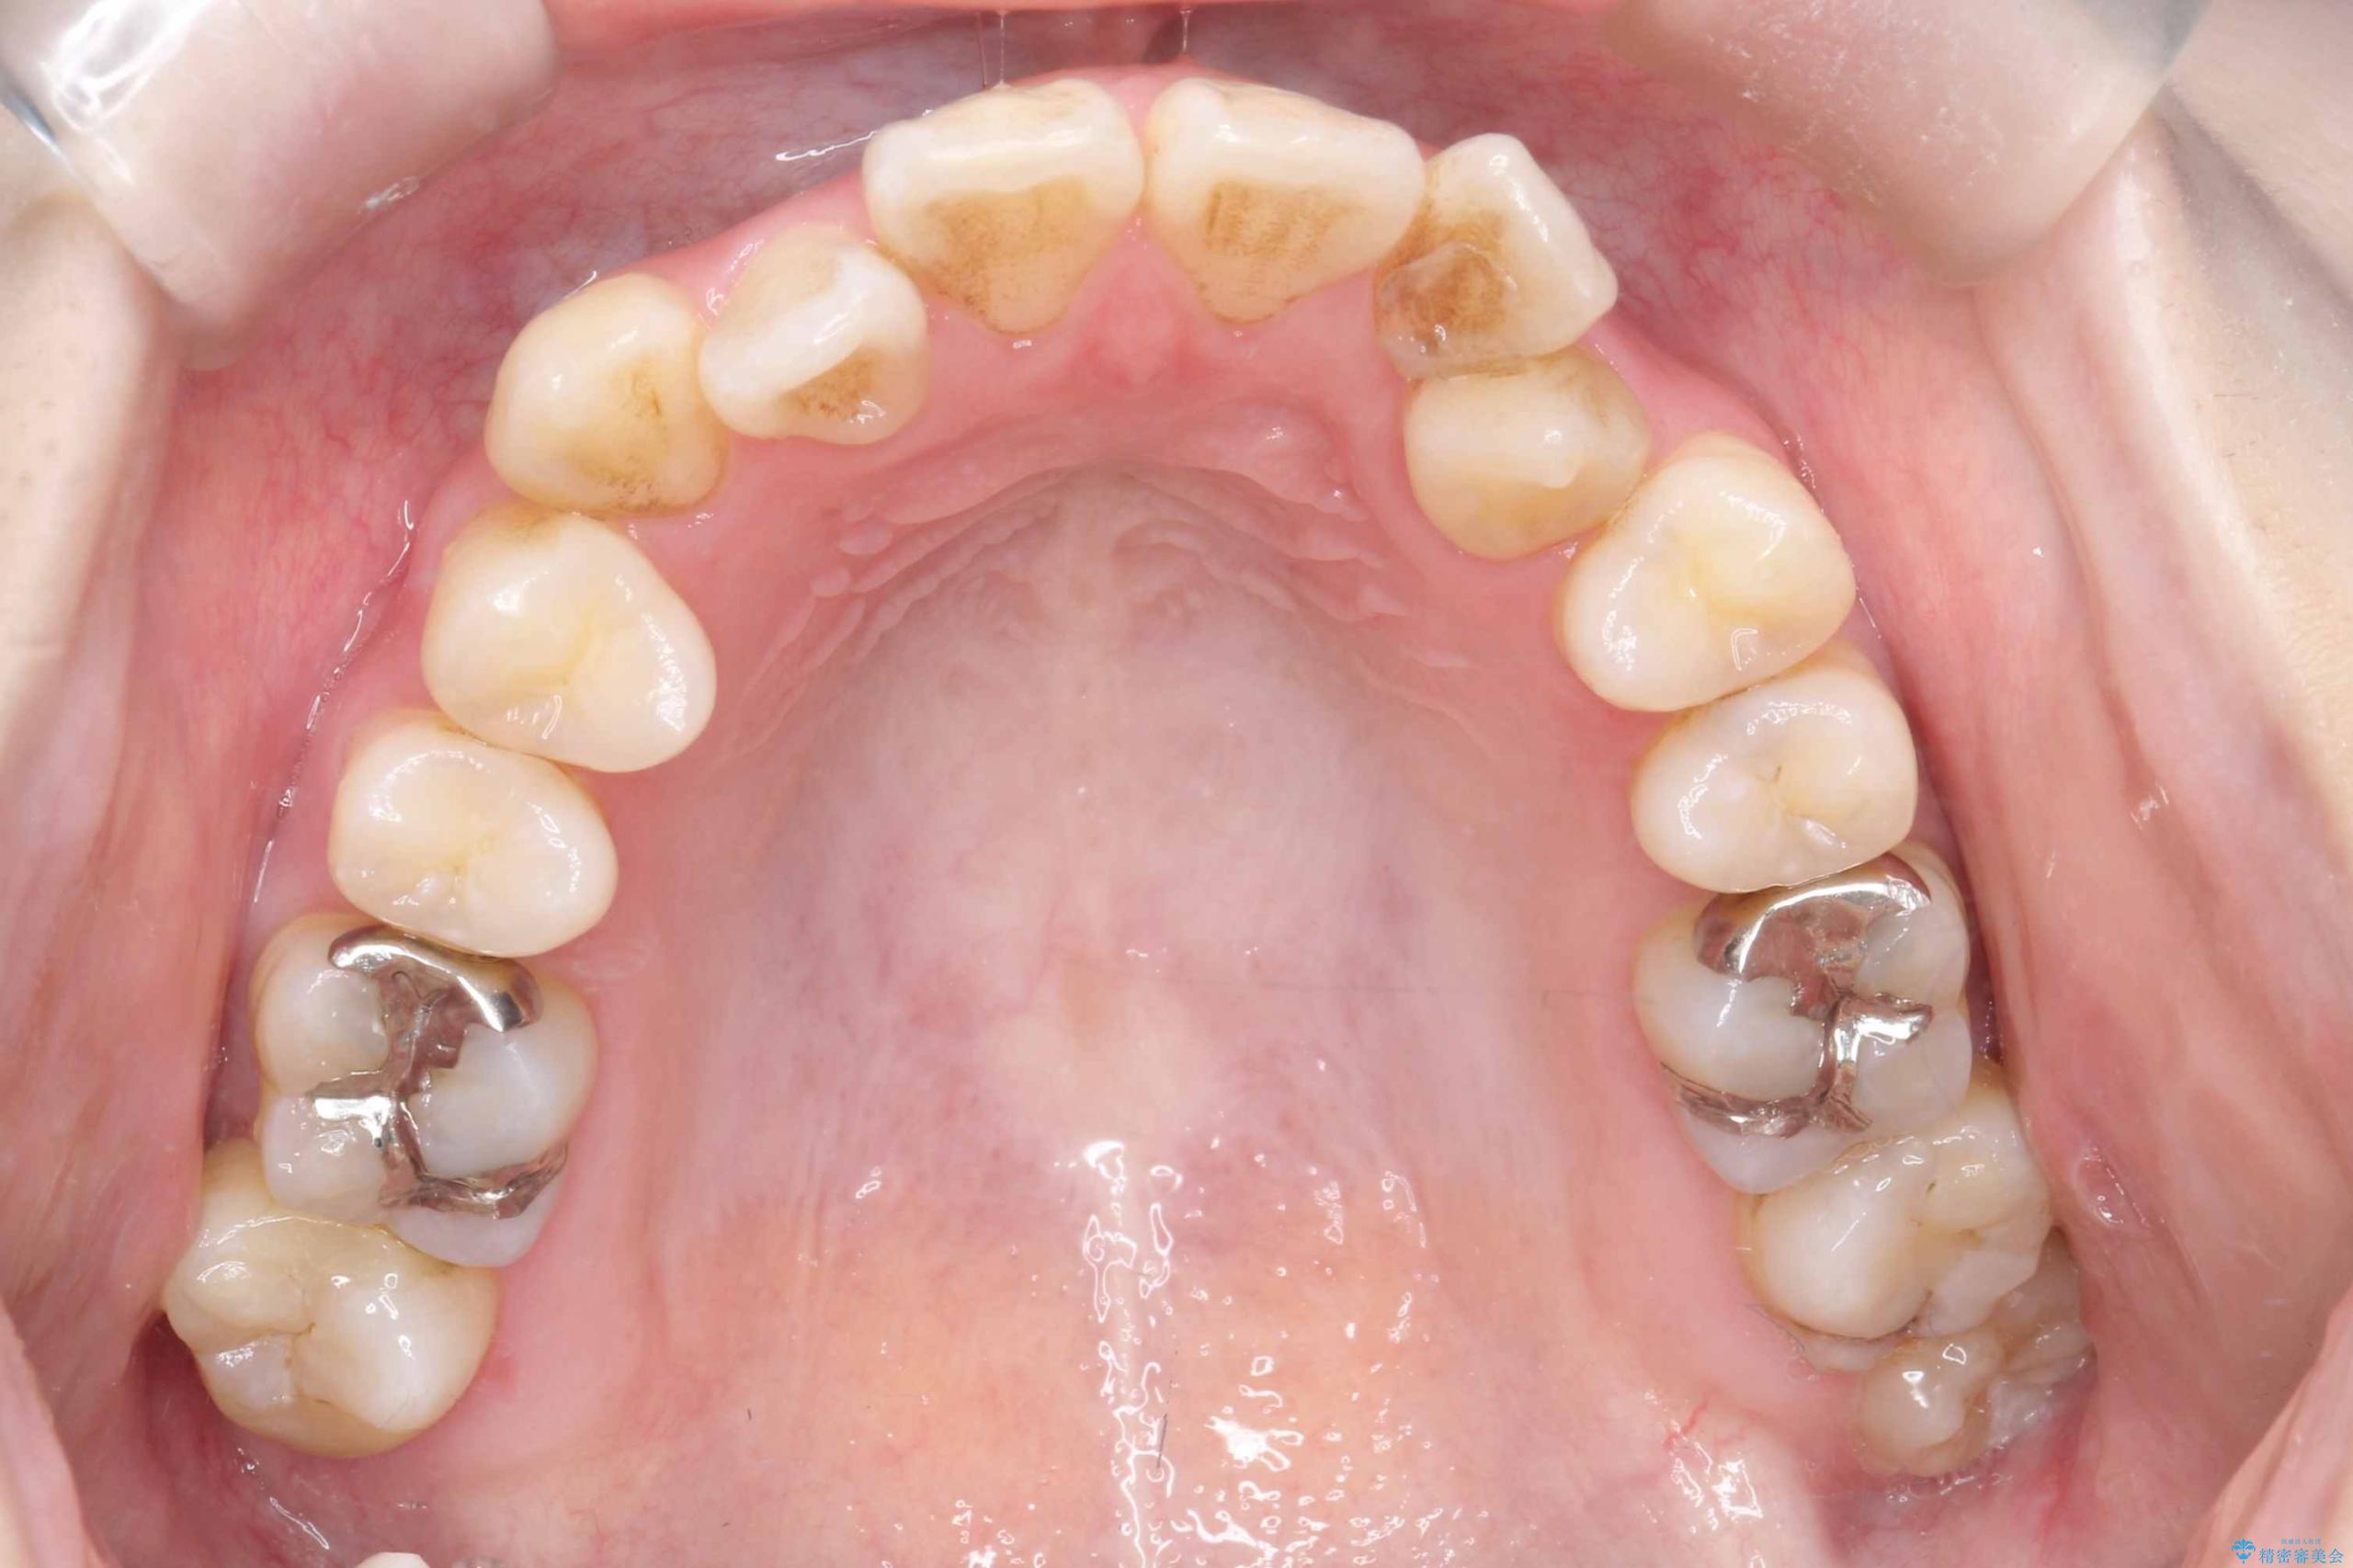

- 開咬と歯のデコボコ(叢生)、八重歯を主訴にご来院された患者様です。

矯正の精密検査の結果、上顎左右4番および下顎左右5番の計4本を抜歯し、ワイヤー矯正(クリア装置)にて治療を行いました。

虫歯があったので、虫歯治療は矯正前に行っています。